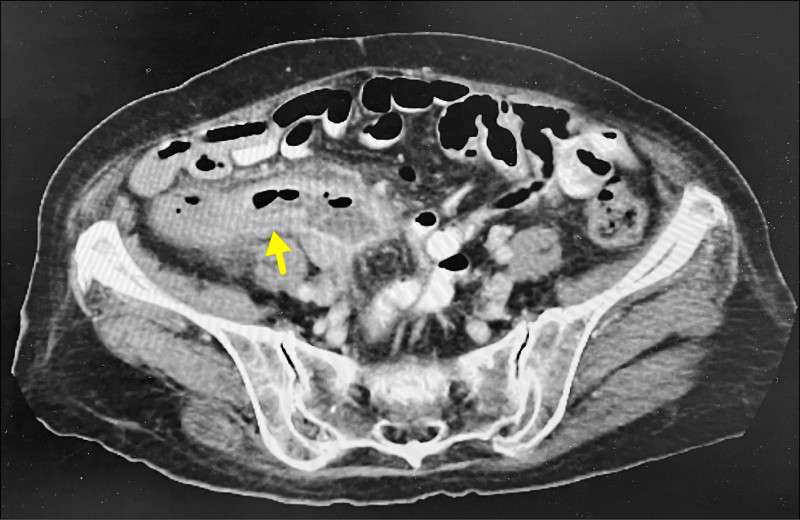

吳阿嬤去年以來右下腹常隱隱作痛,因不想給子女帶來麻煩,能忍就忍,直到上月痛到無法走路,兒子陪同至澄清醫院中港院區胃腸肝膽科門診,抽血檢查發現,血紅素掉到8.7(正常12-16)、白血球15900(正常1萬以下),再經腹部電腦斷層檢查,查出右下腹部有一大團約10公分大腫瘤,外形不規則狀確診大腸癌,並已破裂擴散。

阿嬤住院後,院方緊急會診大腸直腸外科醫師陳周誠,經緊急手術後,發現吳婦的右側大腸腫瘤約5.6公分大,腫瘤鑿穿大腸壁,溢出腫瘤物形成約4.9公分大破裂範圍,也侵犯到迴腸末段,經切除大腸癌患部5公分,受癌細胞侵犯的迴腸55公分,再將小腸和大腸精密吻合,築出新通道,維持腸道暢通。